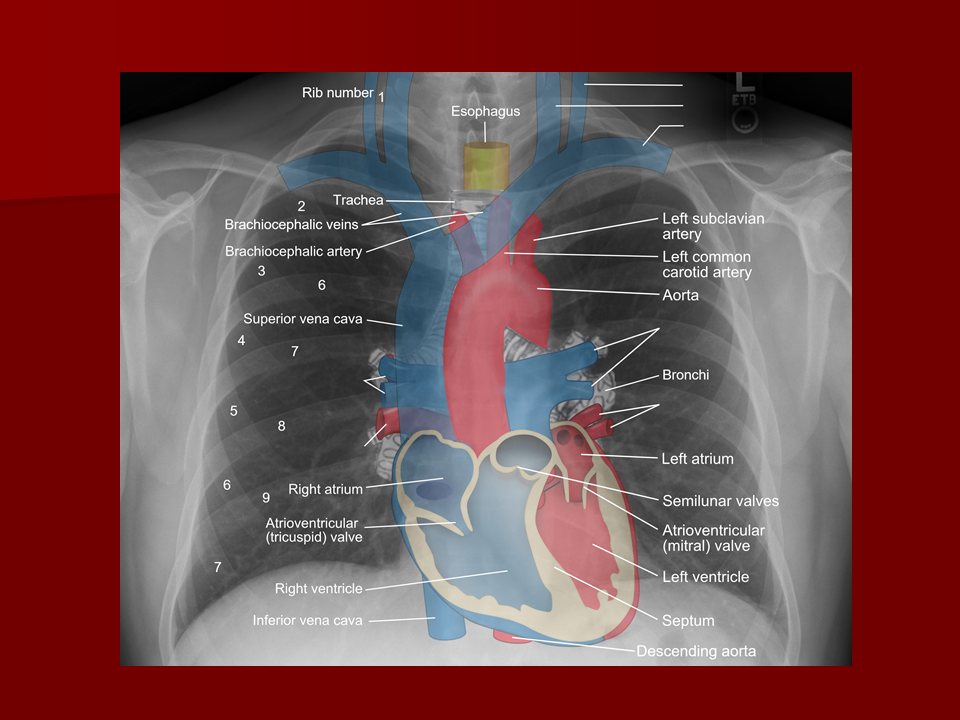

Chest X-ray anatomy